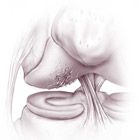

Le rotture meniscali sono tra le più frequenti lesioni interne del ginocchio. Possono essere di tipo degenerativo o traumatico. Esistono diversi tipi di rottura: semplice, a manico di secchia, a lembo (flap), complessa, ecc.

Se la lesione è piccola, situata sul bordo esterno e i sintomi sono scarsi con una buona stabilità del ginocchio, essa può non richiedere un intervento chirurgico ed essere trattata conservativamente. Nelle fasi acute un periodo di riposo funzionale, ghiaccio e antinfiammatori sono sufficienti per alleviare i sintomi. Un programma di rinforzo della muscolatura della coscia è fondamentale per il recupero funzionale.

Nei casi in cui i sintomi dolorosi persistono o nei casi previsti, le rotture meniscali sono trattate anch’esse artroscopicamente con ottimi risultati. Le lesioni più periferiche (nella cosiddetta “zona rossa”) hanno qualche chances di guarire e per questo motivo possono essere suturate (nei pazienti giovani). Le rotture più comuni, tuttavia, avvengono nella zona più interna, la meno vascolarizzata (“zona bianca”); non avendo possibilità di cicatrizzarsi, la parte del menisco rotta viene semplicemente asportata.